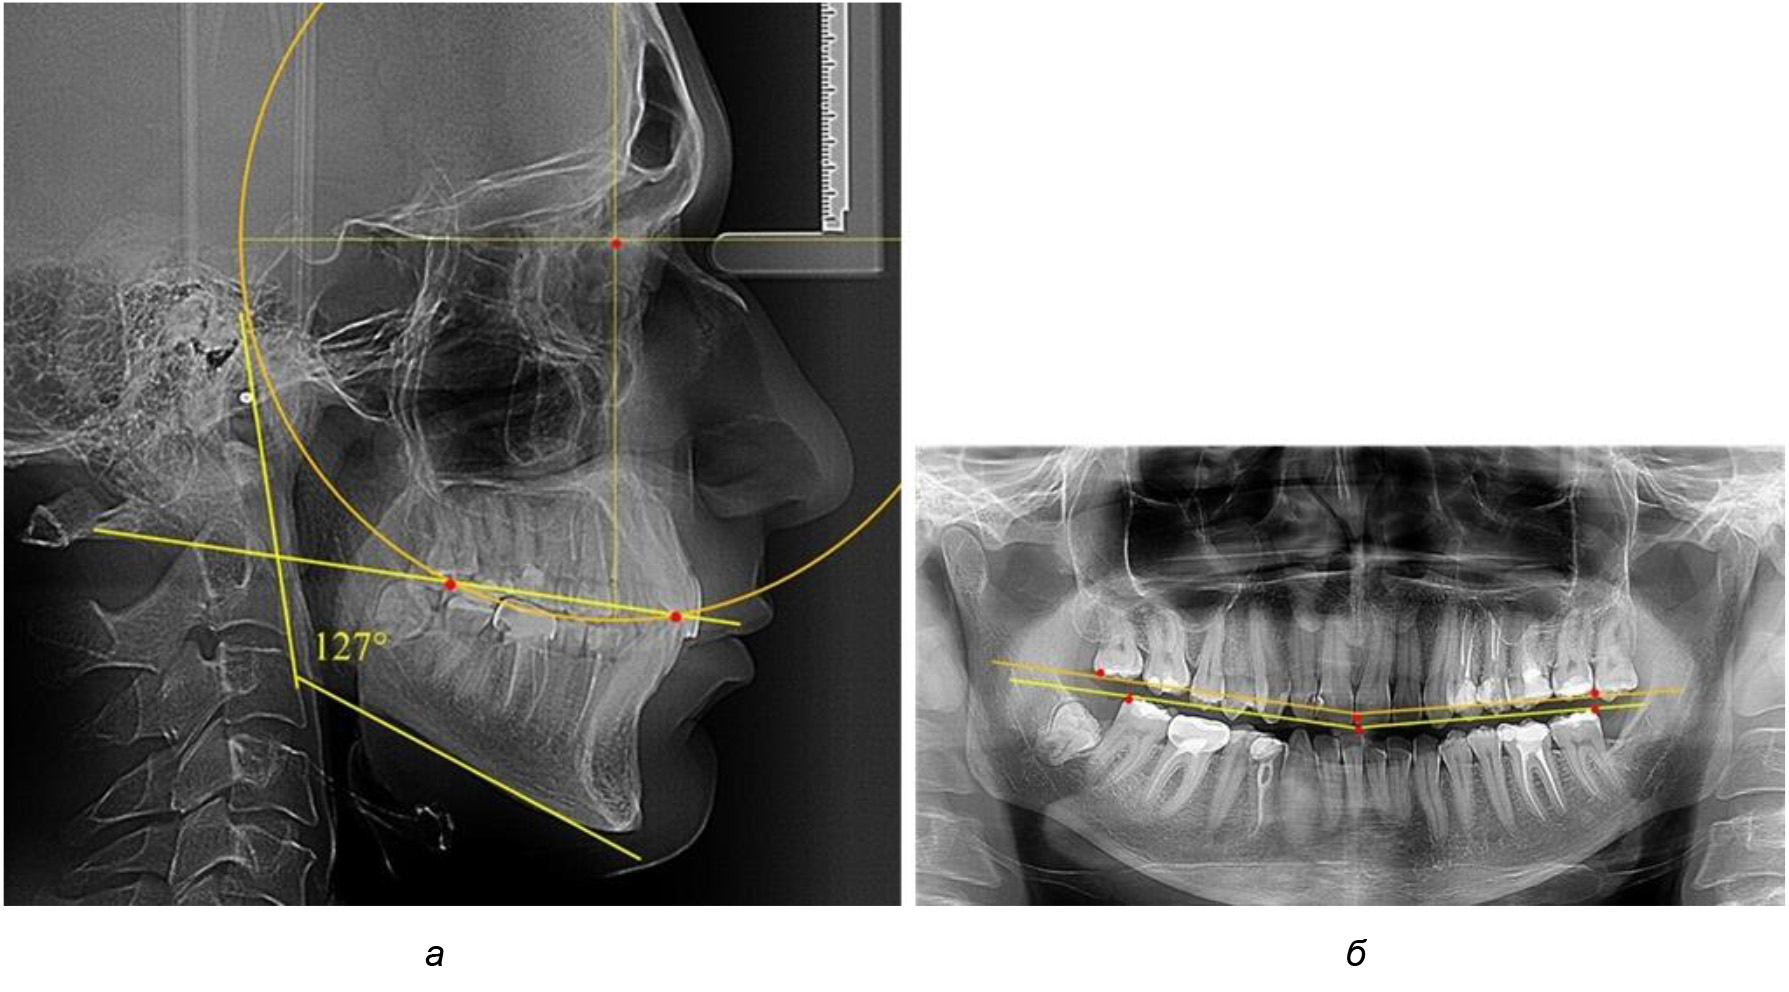

При анализе латеральных ТРГ устанавливали реперный окклюзионные точки в переднем и боковом отделе. Передняя точка устанавливалась на режущем крае нижнего медиального резца, которую в клинике ортодонтии обозначают как vPOcP. Дистальная точка второго нижнего моляра обозначалась как hPOcP. Измеряли расстояние между окклюзионными точками, что определяло сагиттальный размер окклюзионной линии. Использование программ PowerPoint позволило проводить окружность, проходящую по линии смыкания зубов через окклюзионные точки. Измеряли радиус окружности. Учитывая вариабельность размеров окклюзионной линии и радиуса окружности, определяли относительный показатель через отношение радиуса круга к длине сагиттального размера окклюзионной линии. Глубину окклюзионной кривой измеряли от точки наибольшей выпуклости до окклюзионной линии (рис. 1). На ортопантомограмме (ОПТГ) также соединяли окклюзионные точки правой и левой стороны и измеряли глубину окклюзионной кривой от точки наибольшей выпуклости до окклюзионной прямой линии. Результаты глубины кривой Spee сравнивали по данным ТРГ и ОПТГ.

Рис. 1. Метод определения кривой Spee на ТРГ (а) и на ОПТГ (б)

Анализ результатов показал, что глубина кривой Spee в среднем по подгруппе составил (4,12 ± 0,53) мм как при анализе ТРГ, так и ОПТГ.

Деление величины радиуса круга к длине окклюзионной линии составило 1,623 ± 0,02. Таким образом, для определения радиуса окружности, соответствующей кривизне окклюзионного контура боковой ТРГ, необходимо измерить расстояние между передней и задней окклюзионными точками и последующим умножением полученной величины на число Фибоначчи (рис. 2).